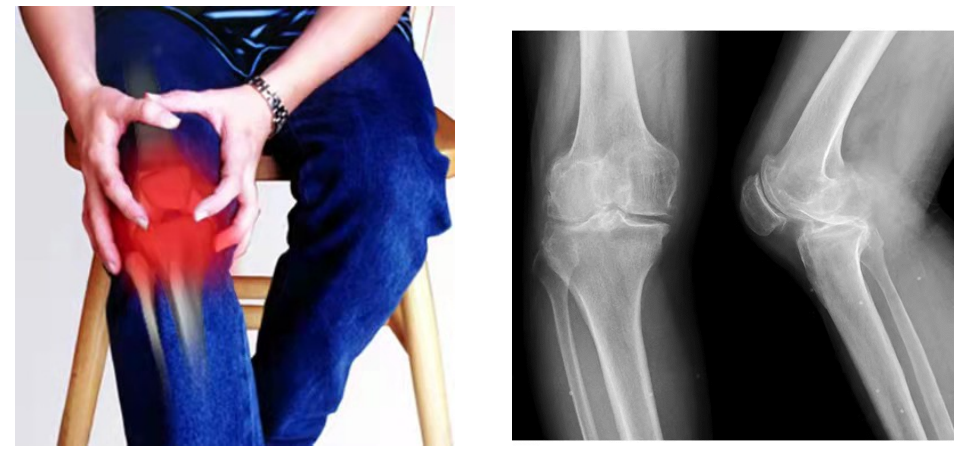

骨性关节炎,在民间也被称为“长骨刺”、“骨质增生”,主要是膝关节过劳、长期处于寒湿状态引起膝关节病变。主要表现为⑴疼痛,痛症为:①起步痛,久坐或刚下床行走时疼痛明显,活动后可缓解;②负重、上下楼梯时疼痛加重;③静息状态也会疼痛,夜间更痛。⑵活动受限,晨僵,即早上起床时自觉关节僵硬,一般持续时间小于30分钟。⑶关节畸形、肿大,早期可见肿胀,中晚期出现畸形。⑷关节屈伸时有骨擦感。